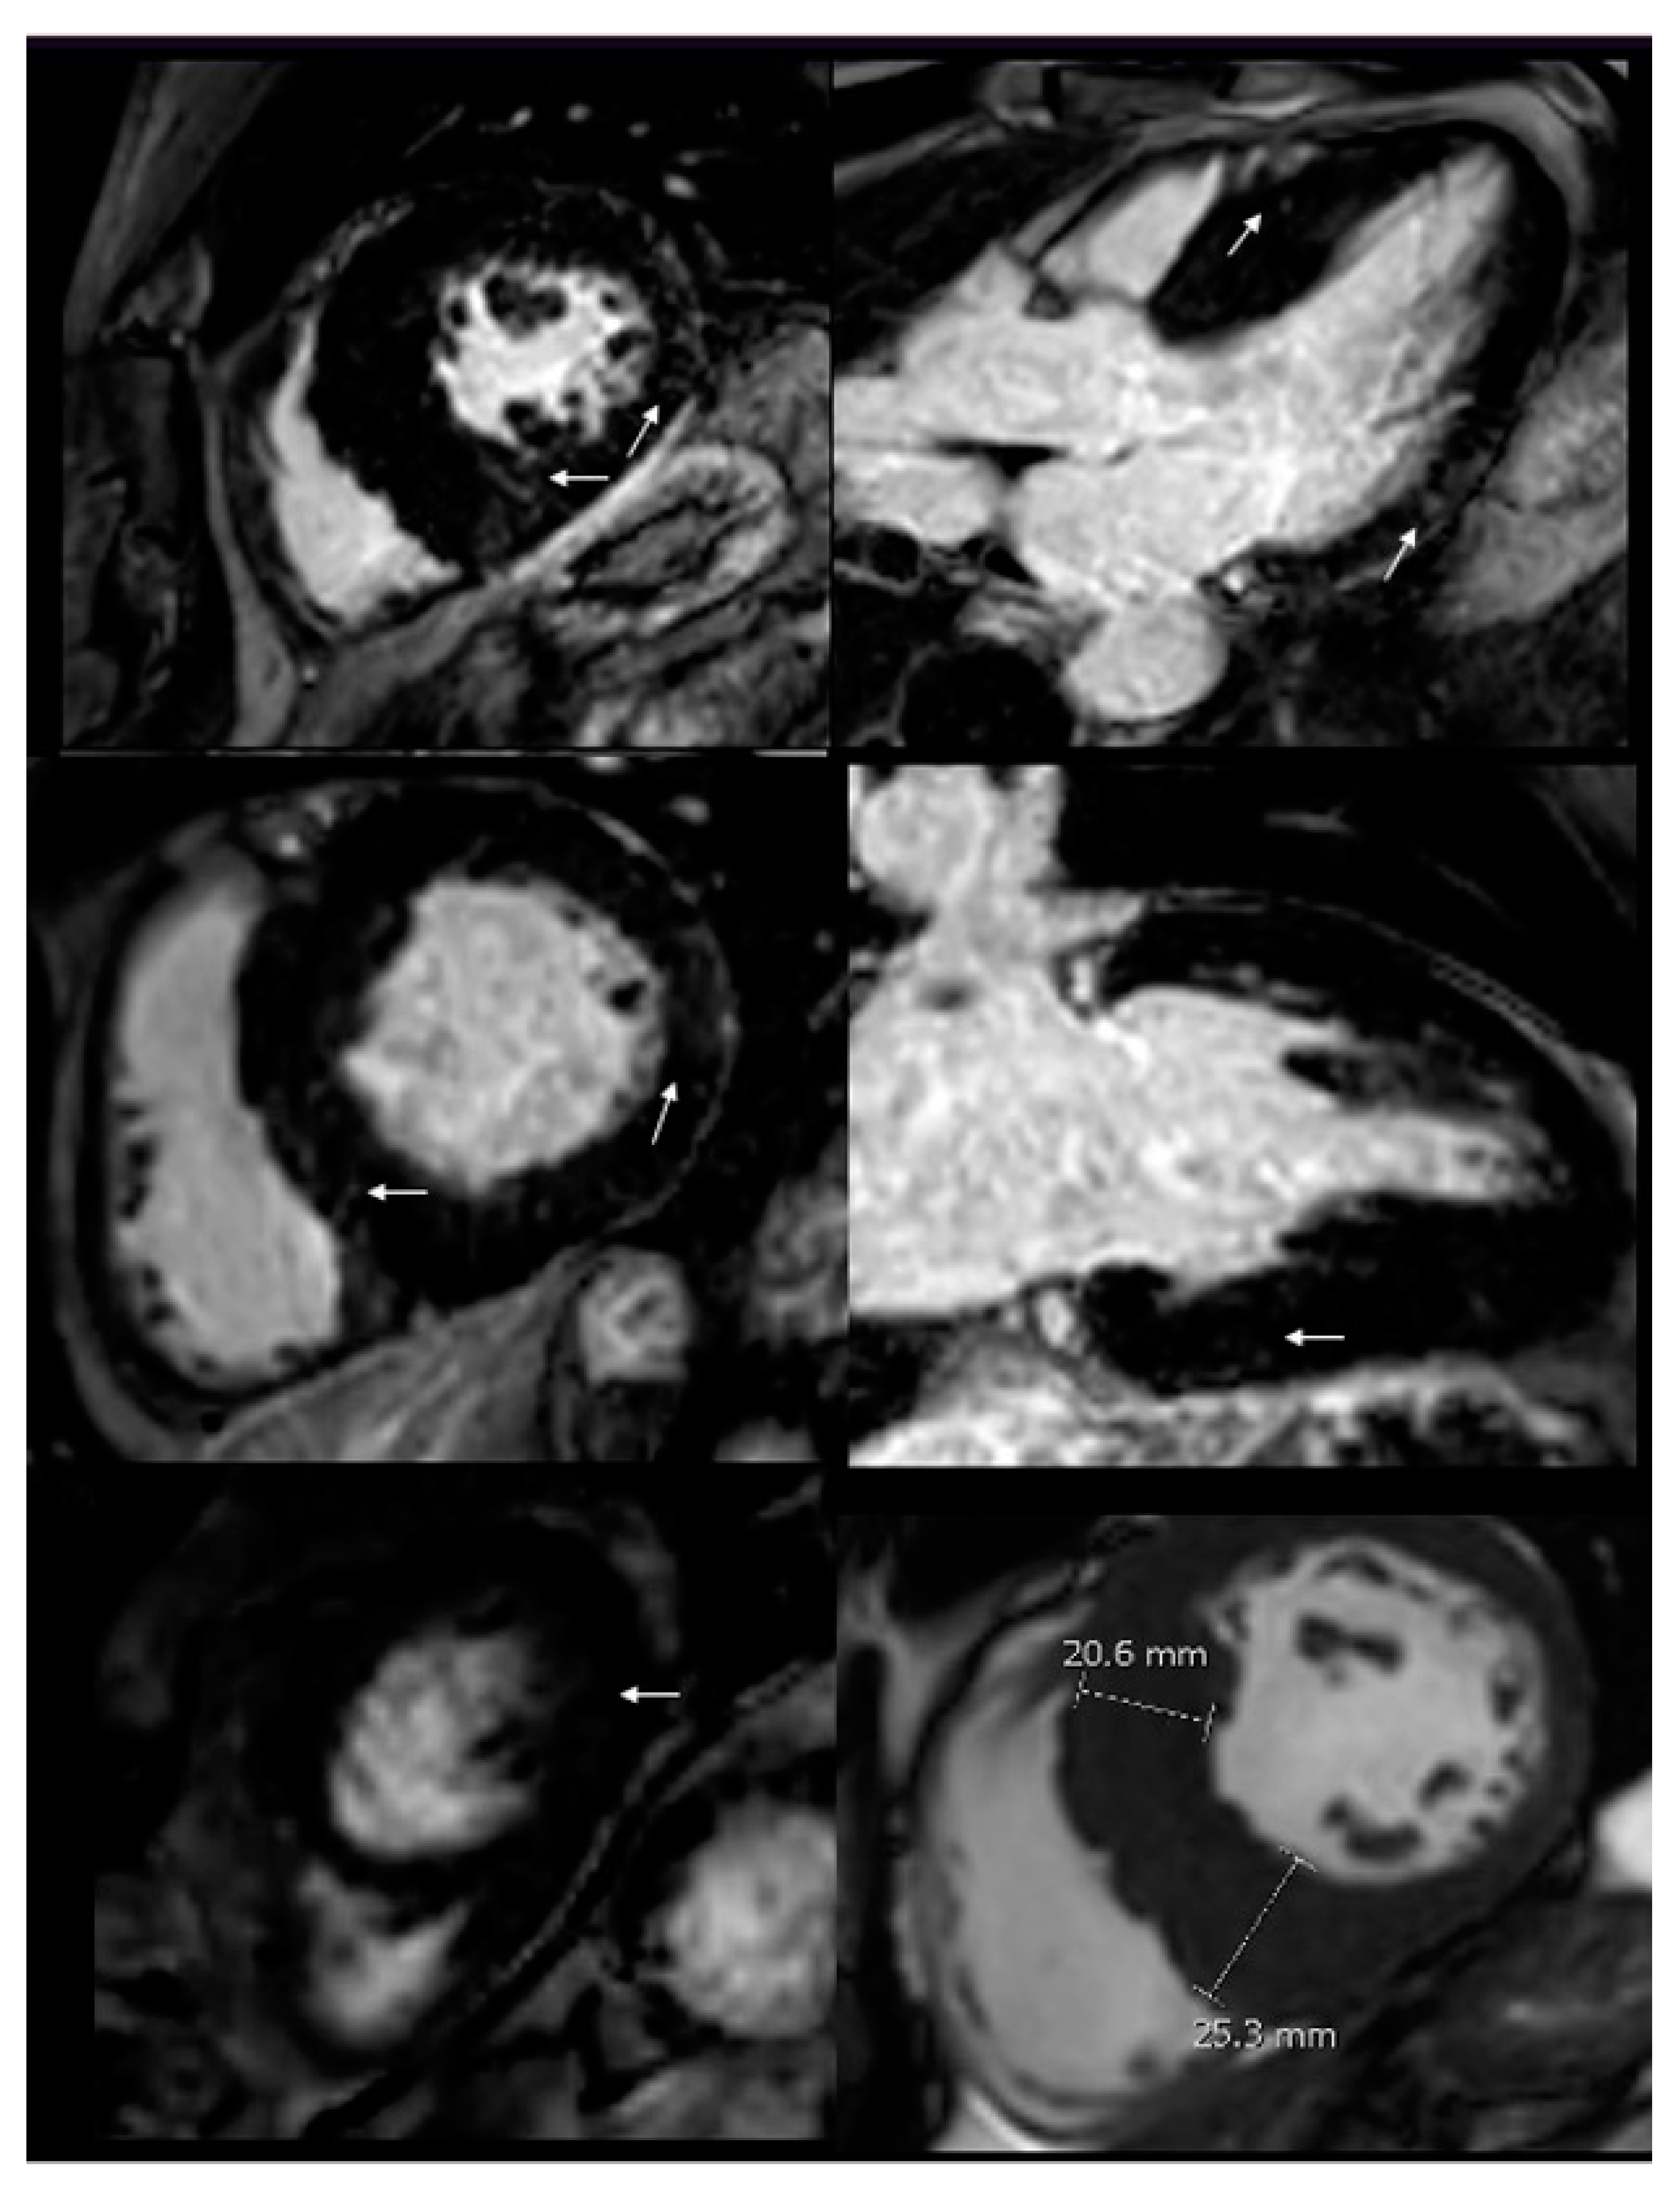

Figure 3. CMR imaging. Increased wall thickness, specially compromising the infero-septal wall, reaching 25 mm in the middle segment. After contrast administration, patchy mid-wall late gadolinium enhancement (LGE) was seen in the inferoseptum, as well as in the basal and mid segments of the anterior, inferolateral and inferior wall. (White arrows).

52-year-old man with history of hypertension since the age of 35 years, with no other significant personal or family history, under outpatient cardiology treatment, with regular blood pressure control, presented during follow-up studies exercise dyspnea. Studies were done, with an ECG showing left ventricular hypertrophy (LVH), and short PR interval (Figure 1). Transthoracic echocardiogram (TTE) evidenced increased end-diastolic thickness -basal infero-septal wall of 23 mm and basal anteroseptal wall of 21 mm (Figure 2), findings suggestive of HCM. For this reason, he was referred to our cardiac imaging laboratory, with indication of cardiac magnetic resonance, as a complementary study for HCM. CMR showed increased wall thickness, specially compromising the infero-septal wall, reaching 25 mm in the middle segment, without wall motion abnormalities, with normal left ventricle systolic function, LVEF: 64%. There was not systolic anterior motion of the mitral valve, and apical insertion of the papillary muscles was noted. Right ventricle wall thickness and systolic function was normal, RVEF: 72%. After contrast administration, patchy mid-wall late gadolinium enhancement (LGE) was seen in the inferoseptum, as well as in the basal and mid segments of the anterior, inferolateral and inferior wall. Findings suggestive of asymmetric septal HCM. At that time, our center did not have parametric mapping. With these findings, he was referred to our heart failure clinic for complementary studies. As part of the approach to the patient with hypertrophic phenotype, a next-generation sequencing (NGS) panel was requested.

Extra-cardiac involvement includes vessels, kidneys, and peripheral nervous system (6-8). ECG findings other than LVH, such as duration of the P wave < 80 ms and PQ interval < 140ms (as in our patient) have an area under the curve of 0.81-0.92, sensitivity of 80-92% and specificity of 70-80%, respectively. They are useful in early detection, even in the absence of LGE (8). Late onset FD phenotype could present with LVH and papillary muscle hypertrophy mimicking HCM and longitudinal myocardial deformation of the basal segments. The multimodality approach in FD patients is essential, so the use of imaging such as CMR not only provides greater accuracy in the measurement of ventricular wall thickness and can visualize myocardial fibrosis typically distributed in the mid-myocardial layer of the posterolateral wall and extent of fibrosis has been correlated with the degree of response to enzyme replacement therapy (7). The use of tools such as T1 mapping allows the detection of early changes in the cardiac muscle interstitium, and low values, especially at the septal level, have been found in patients with FD, and it is believed that this is directly related to the increase in myocardial lipid tissue (10), thus implying earlier recognition of cardiac involvement by FD. In view of this, the systematic use of CMRI in patients with HP may help to reclassify patients. In this patient and in other with HP phenotype, allowing better risk stratification and therapy targeting. An increased left ventricular end-diastolic thickness with a normal or low T1 mapping such as the one noticed in this patient, should make the clinician suspect and test for FD.